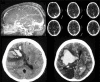

Figure 2

Magnetic resonance imaging brain venogram showing superior sagittal sinus thrombosis and hemorrhagic conversion of venous infarct and computed tomography brain showing superior sagittal sinus thrombosis evidenced by empty delta sign